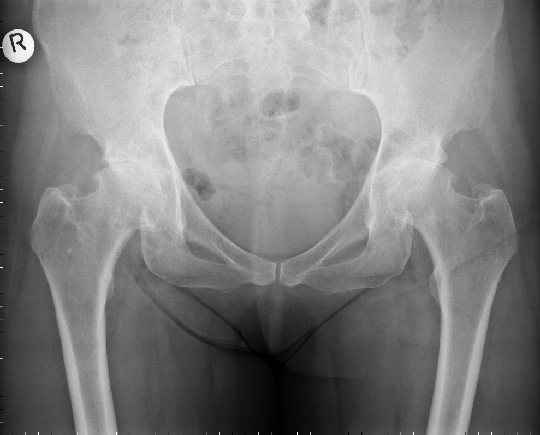

Oltre all'esame clinico servono per la diagnosi delle radiografie dell'anca

Solo in casi rari bisogna ricorrere ad una risonanza magnetica.